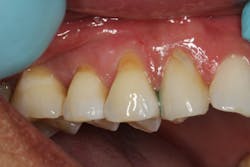

A 45-year-old male presented for three class V fillings. Teeth nos. 4 and 5 had cervical abrasions (or erosion), and no. 6 had a defective existing composite fillingThe teeth to be restored in this case had excellent gingival health, and the patient was in good health. The patient was anesthetized with one carpule (1.7 ml) of lidocaine with 1:100,000 epinephrine.

The composite material will appear too white or high in value at first, but after light curing, the composite blends into the color of the natural teeth. A thin interproximal carver was used to carefully seal the gingival margins of the restorations and follow the contour of the natural tooth. This process is made easier by the handling properties of the composite material, which stays in place and doesn’t slump. The material was thoroughly light cured on all three restorations (figure 3).